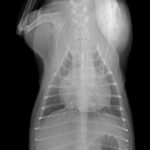

9歳の柴犬が散歩中に突然倒れる事があるとのことでかかりつけを受診しました。幼少時よりてんかん発作を発症する事があるが、今回の様子はてんかんの時とは異なる様だとのことで精査を希望され来院しました。心音は微弱でマッフルを呈していました。また、腹水の貯留も確認されました。心臓超音波検査では心膜液の貯留が確認されました。心嚢水の除去を行なったところ、出血性の心嚢水でした。数日間は心嚢水の除去のみで一般状態は改善していました。しかし、再発すると虚脱するといった症状が確認されたため、再発性の心タンポナーゼを回避するために、胸腔鏡下で心膜切除術を実施しました。同時に中皮腫、血管肉腫、特発性との鑑別にCTによる精査も実施しております。心膜の病理検査では腫瘍性の変化はなく、著しく繊維化した心膜であり、特発性と診断されました。胸腔鏡下での手術であったため、数日間の入院で痛みも少なく良好に経過しています。